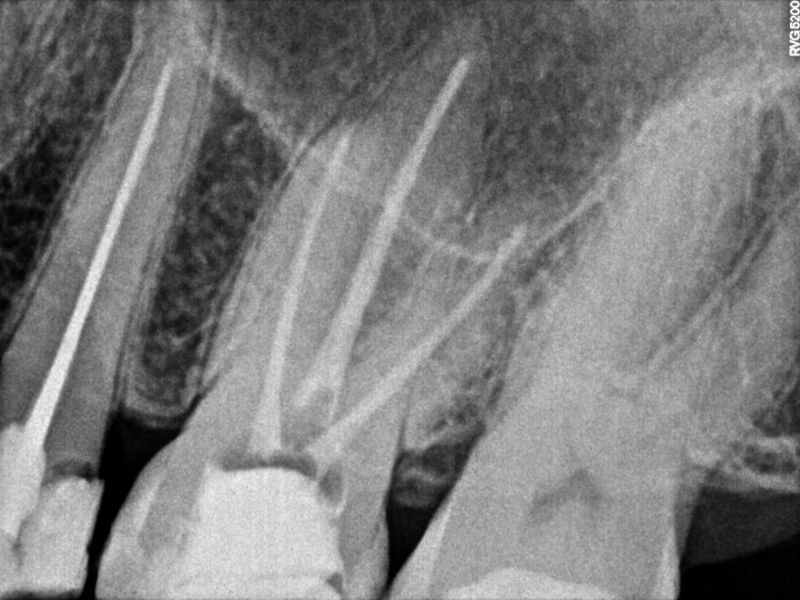

Nuestro Trabajo